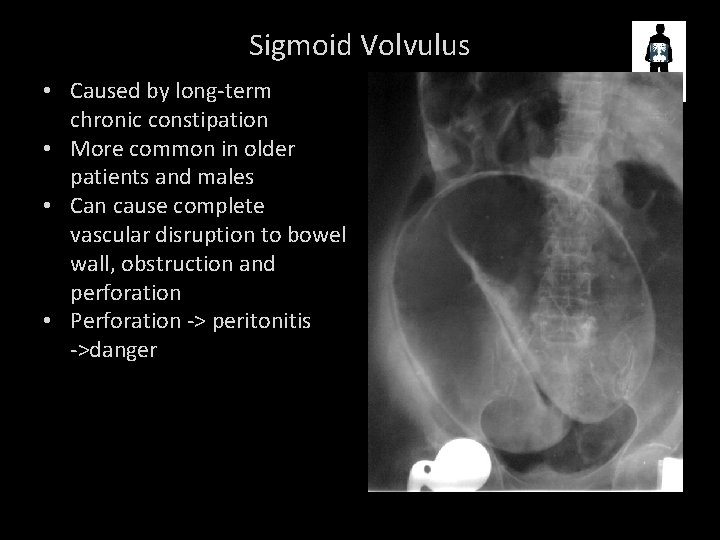

SIGMOID VOLVULUS Large bowel obstruction – sigmoid colon twists on itself COFFEE BEAN SIGN

Sigmoid Volvulus • Caused by long-term chronic constipation • More common in older patients and males • Can cause complete vascular disruption to bowel wall, obstruction and perforation • Perforation -> peritonitis ->danger